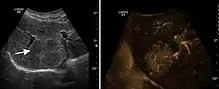

Hemangioma

It is the most common liver tumor with a prevalence of 0.4 – 7.4%. It is generally asymptomatic but also can be associated with pain complaints or cytopenia and/or anemia when it is very bulky. It is unique or paucilocular. It can be associated with other types of benign liver tumors. Characteristic 2D ultrasound appearance is that of a very well defined lesion, with sizes of 2–3 cm or less, showing increased echogenity and, when located in contact with the diaphragm, a "mirror image" phenomenon can be seen. When palpating the liver with the transducer the hemangioma is compressible sending reverberations backwards. Doppler exploration reveals no circulatory signal due to very slow flow speed. CEUS investigation has real diagnosis value due to the typical behavior of progressive CA enhancement of the tumor from the periphery towards the center. The enhancement is slow, during several minutes, depending on the size of hemangioma and on the presence (or absence) of internal thrombosis. During late (sinusoidal) phase, if totally "filled" with CA, hemangioma appears isoechoic to the liver. Deviations from the above described behavior can occur in arterialized hemangiomas or those containing arterio-venous shunts. In these cases, differentiation from a malignant tumor is difficult and requires other imaging procedures, follow up and measurements of the tumor at short time intervals.[4]